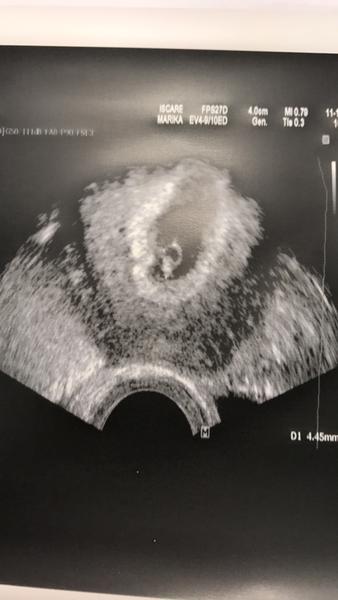

Podavam hlaseni! Rybicka ma 5mm, tluce ji krasne srdicko. Podle ms jsem 6+5tt, podle velikosti 6+1 a podle ovulace 5+6tt...no proste prcek by mel vykouknout nekdy v cervenci 2017. Ve ctvrtek posledni kontrola v Iscaru. Mam se objednat do poradny... Malem mi ukapla slza, vsichni byly skvely!! Jsem z toho cela namekko...

@lussinka88 no to je krásná fotečka, držím pěsti, aby bylo vše v pořádku 😊

@lussinka88 to je nádherná fotka. Až mi ukápla slzičky. No vidíš takových možností 😂 moc moc držím palecky ať je vše v pořádku a v červenci si budeme ukazovat ty naše bobany 😉

@lussinka88 to je bobíšek , zamávej Iscaru i nám a pa , pa . Teď už to bude jen lepší 😉